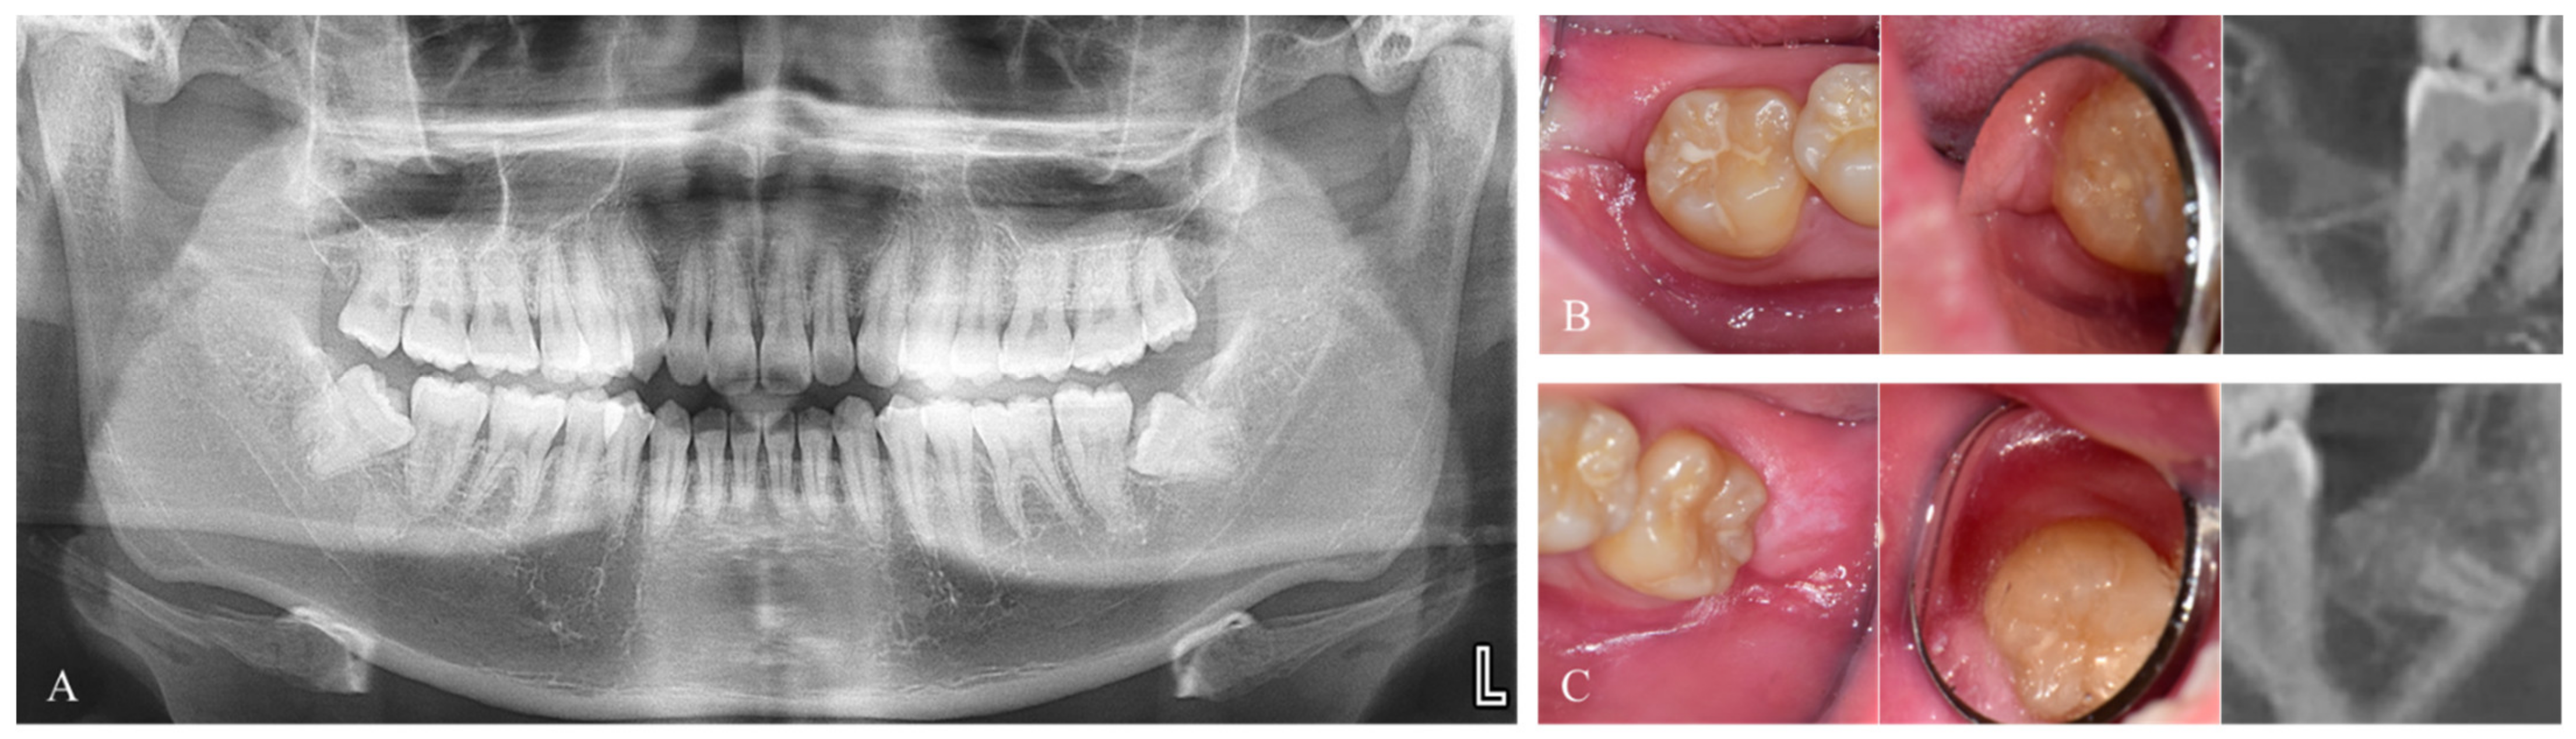

2.1.1. Immediate Graft

2.1.2. Delayed Graft